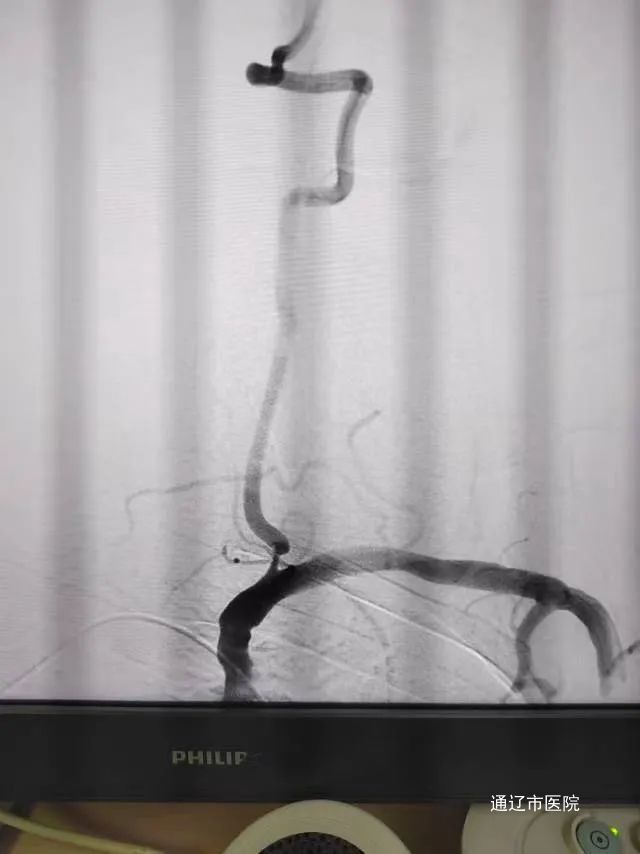

该患者老年男性,既往有脑动脉粥样硬化的风险因素,脑血管造影评估后提示左侧大脑中动脉分叉处狭窄,血管内有少量新鲜血栓,因未见大血管闭塞,而血流速度也在正常范围内,给予超选择经导管脑动脉溶栓治疗。术后患者瘫痪肢体力量明显改善,言语较前流利。溶栓顺利结束,无不良并发症。